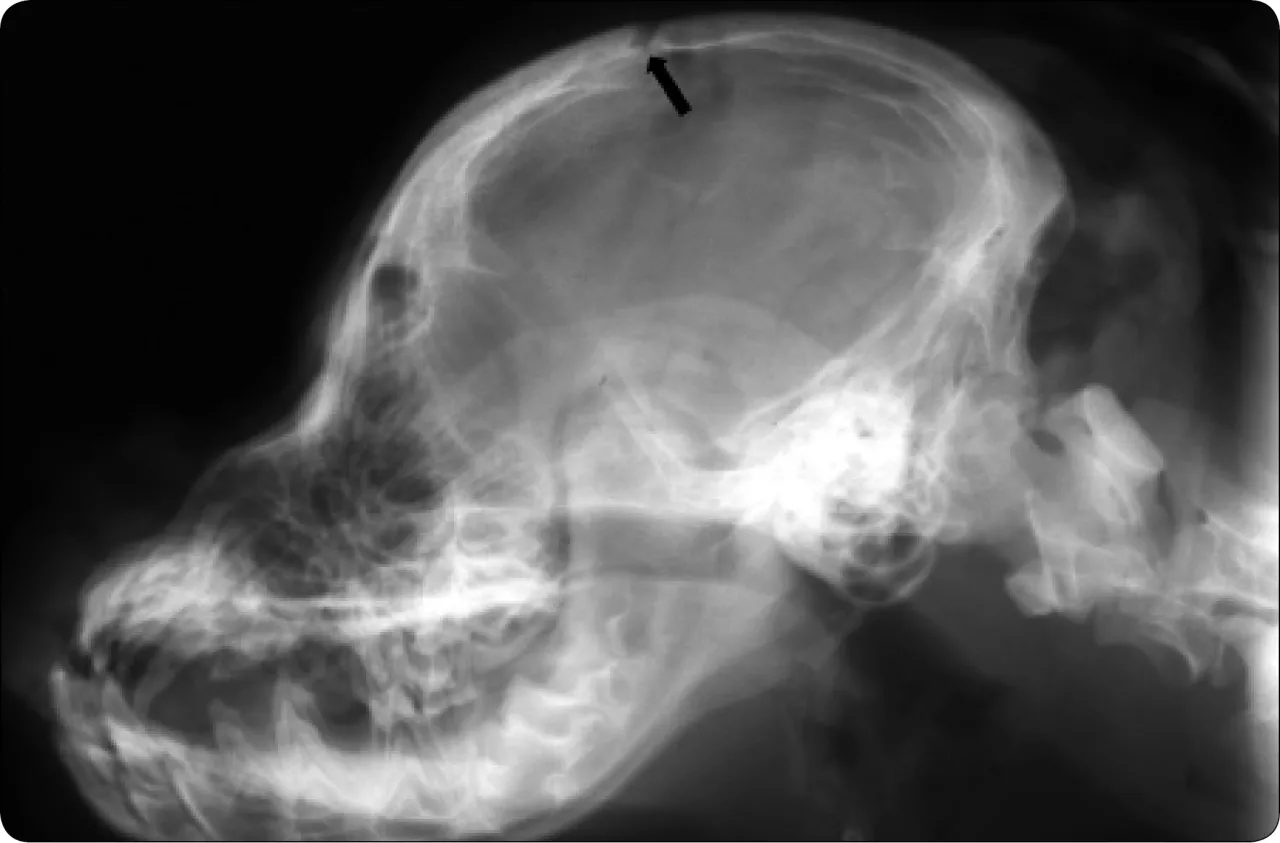

Molera, czyli ciemiączko, to nic innego jak niezrośnięte, łącznotkankowe spojenie kości czaszki. U nowonarodzonych szczeniąt jest to cecha całkowicie fizjologiczna. Kości czaszki nie są jeszcze w pełni zrośnięte, a przestrzeń między nimi wypełnia elastyczna tkanka. U większości ras to ciemiączko zarasta w ciągu kilku tygodni lub miesięcy po urodzeniu. Jednak u rasy chihuahua sytuacja wygląda nieco inaczej. Jest ono tak powszechne u tych maluchów dotyczy nawet 80-90% osobników, zwłaszcza tych z charakterystyczną głową w kształcie jabłka że Amerykański Kennel Club (AKC) w swoim wzorcu rasy dopuszcza jego obecność. To oznacza, że samo w sobie ciemiączko nie jest wadą ani chorobą, ale musimy pamiętać, że stanowi ono istotny czynnik ryzyka, o czym opowiem za chwilę.

Jak wspomniałem, u większości szczeniąt ciemiączko zarasta w ciągu kilku tygodni do kilku miesięcy po urodzeniu, zazwyczaj do około 6 miesiąca życia. Jeśli jednak u Twojego chihuahua pozostaje ono niezarośnięte, oznacza to, że mózg w tym miejscu nie ma pełnej ochrony kostnej. Zamiast twardej kości, jest tam jedynie delikatna tkanka. To sprawia, że głowa psa jest znacznie bardziej podatna na urazy. Chcę podkreślić, że samo otwarte ciemiączko nie jest chorobą, ale stanem, który znacząco zwiększa podatność na poważne urazy głowy. To kluczowa informacja, którą każdy właściciel chihuahua powinien mieć na uwadze.

To bardzo ważne rozróżnienie, które często budzi niepokój. Duże, przetrwałe ciemiączko może być jednym z objawów wodogłowia (hydrocephalus). Wodogłowie to poważna wada wrodzona, polegająca na nadmiernym gromadzeniu się płynu mózgowo-rdzeniowego w komorach mózgu, co prowadzi do zwiększonego ciśnienia wewnątrzczaszkowego i uszkodzenia tkanki mózgowej. Rasy miniaturowe, w tym chihuahua, są niestety predysponowane do tej choroby.